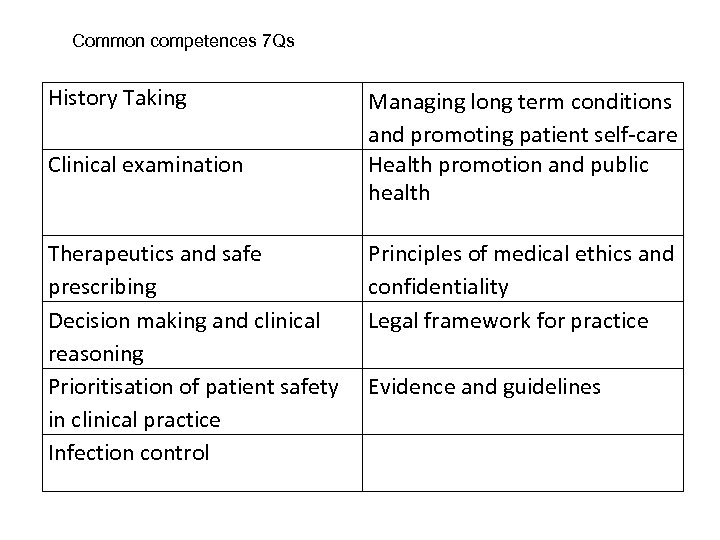

Common competences 7 Qs History Taking Clinical examination Therapeutics and safe prescribing Decision making and clinical reasoning Prioritisation of patient safety in clinical practice Infection control Managing long term conditions and promoting patient self-care Health promotion and public health Principles of medical ethics and confidentiality Legal framework for practice Evidence and guidelines